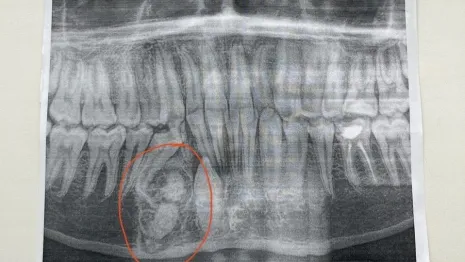

Опухоль с 30 лишними зубами выросла у ребенка из Владимирской области. Мальчика спас челюстно-лицевой хирург ОДКБ Андрей Мухин, сообщила пресс-служба медучреждения в четверг, 8 августа.

Новообразование появилось у малыша в нижней челюсти. Саму опухоль и зубы пришлось удалять с помощью операции.

И это – редкий случай. Обычно лишних зубов один-два. Как правило, это передние зубы верхней челюсти. У мальчиков полиодонтия, или гипердонтия, встречается несколько чаще. А в целом появление сверхнормативных зубов наблюдается примерно у 6% населения.